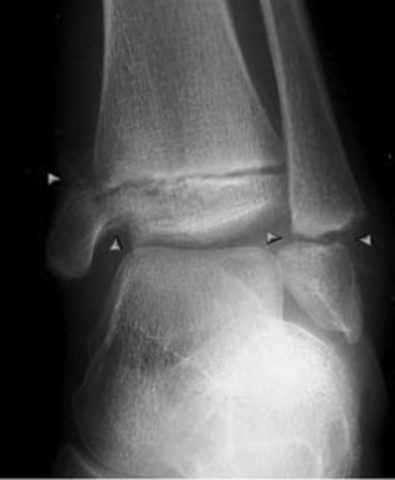

• I broke my growth plate in my ankle

I broke my growth plate in my ankle

During football I broke my growth plate in my ankle. It was only the third day of pads. It affected me because it was my first broken bone